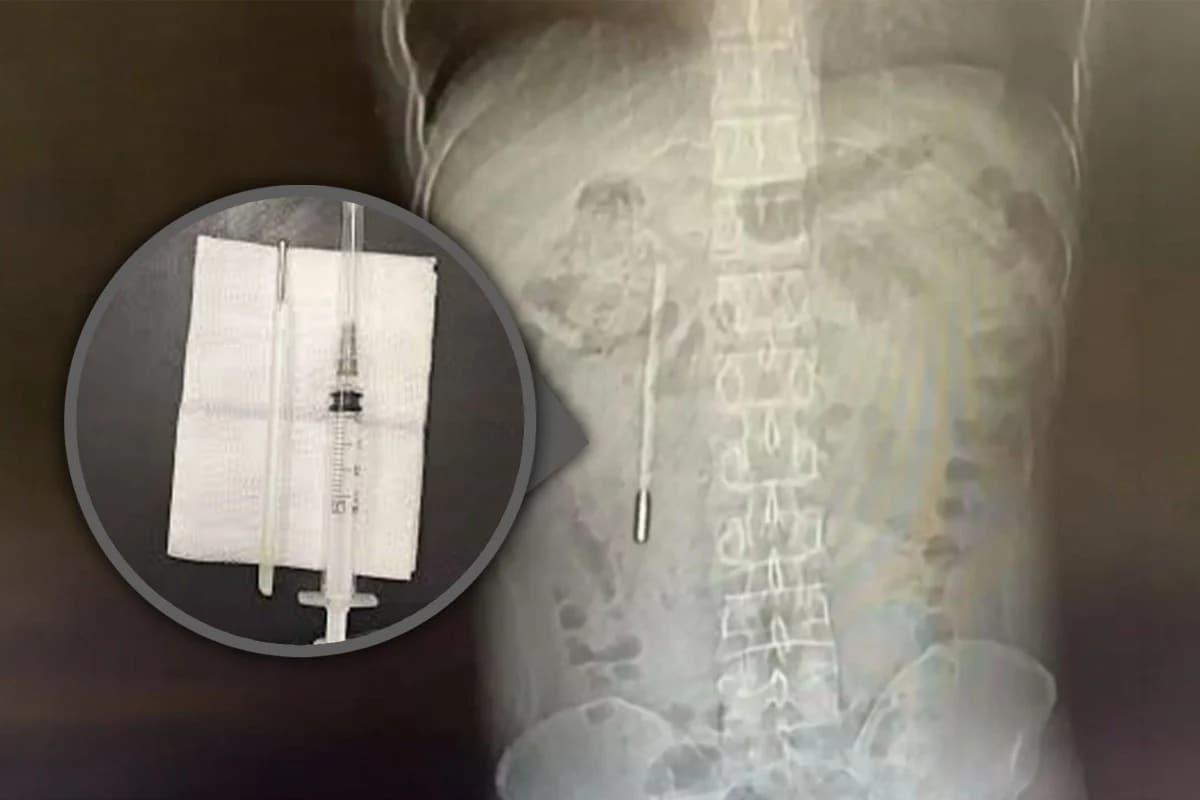

복통 호소한 남성, 배 속서 20년 전 삼킨 '수은 온도계' 나왔다